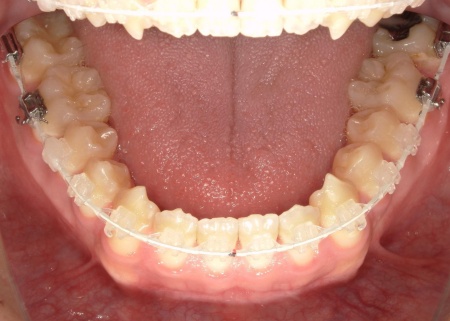

患者様は「できるだけ目立ちにくい装置を使用したい」とのことから、②のセラミックブラケット矯正を選択されました。

まず、下奥歯(臼歯)を歯茎の外側に持ち上げる「挺出(ていしゅつ)」という処置を行いました。

奥歯が少し高くなることで、下顎全体がわずかに後ろへ動くため、前歯の噛み合わせが整いやすくなります。

加えて、上下の前歯には「IPR」という処置を行いました。これは、歯の表面のエナメル質をごくわずかに削り、歯を動かすためのスペースを作る方法です。

このスペースを利用して前歯を後方へ移動させ、審美性の改善を目指しました。